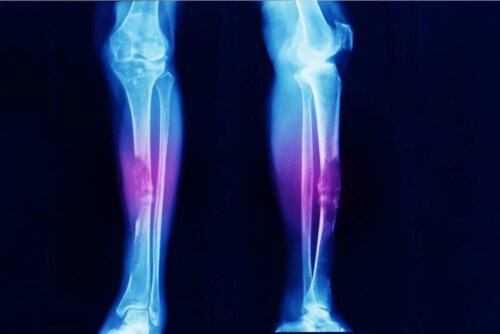

- Osteosarkom er, som navnet tilsier, beinkreft.

Sarkom er ikke vanlig. Faktisk indikerer forskjellige studier at osteosarkom (en svulst i skjelettet) representerer bare 0,2% av alle ondartede kreftformer. Dette betyr at det er en forekomst på omtrent tre tilfeller per million mennesker hvert år.